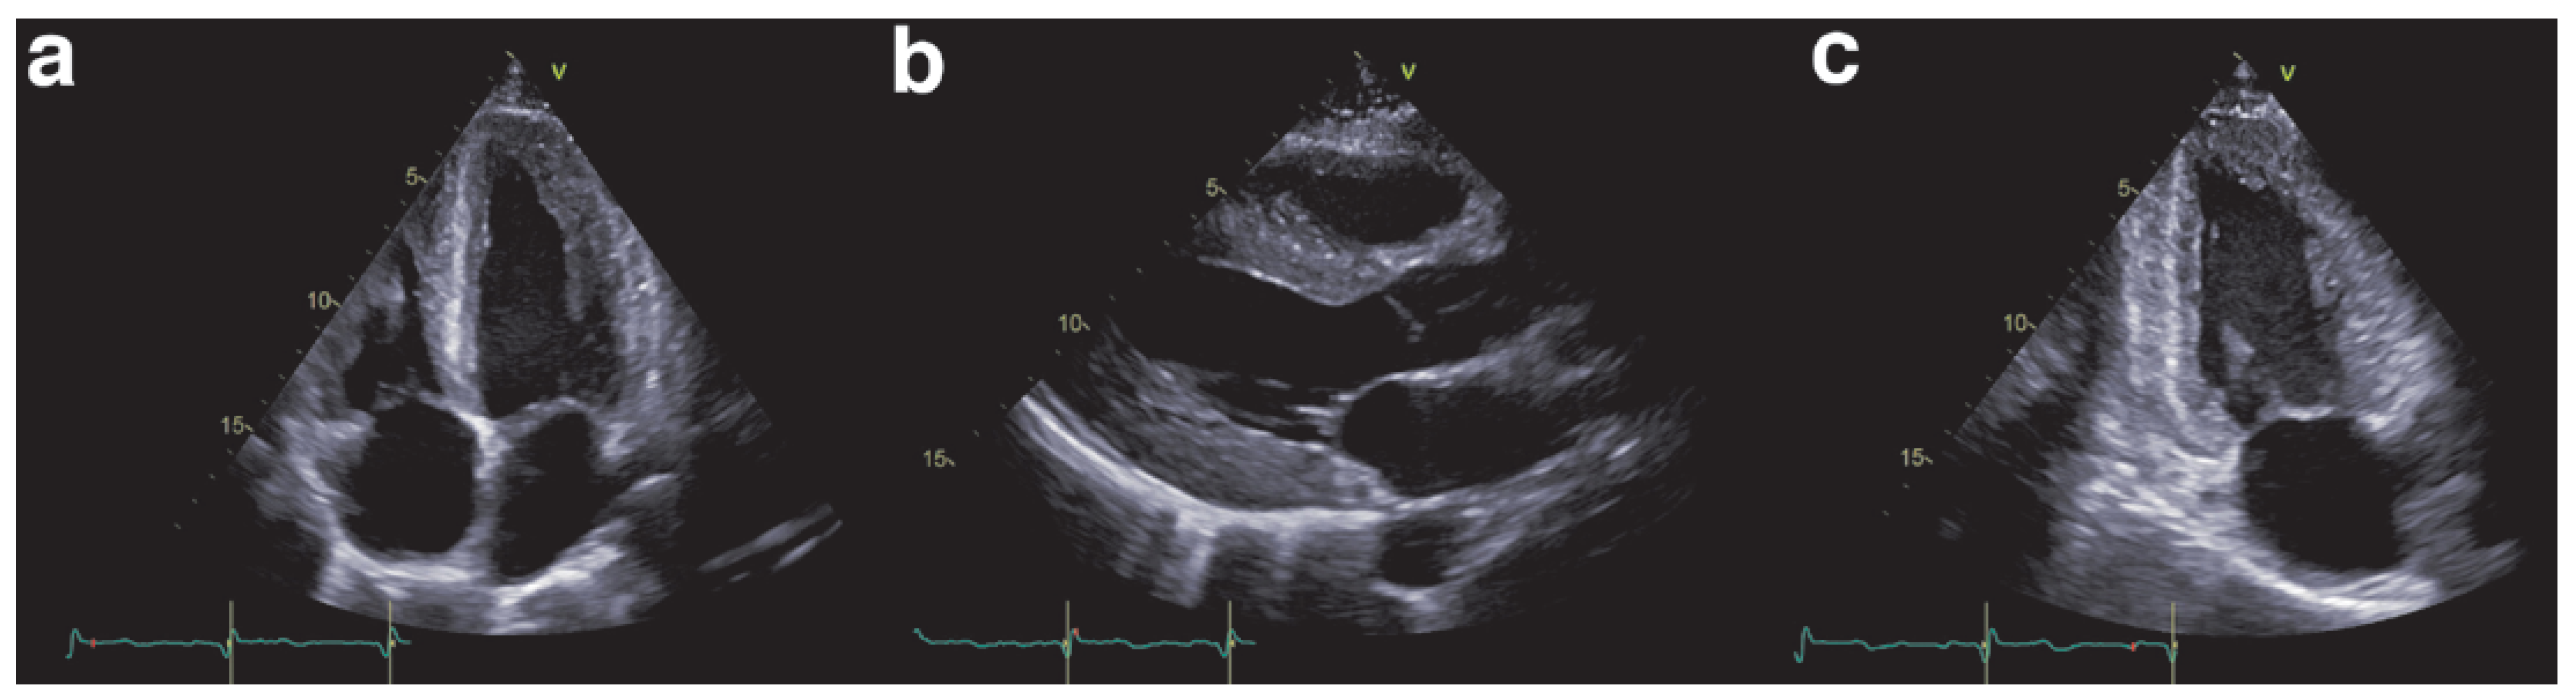

Echocardiography is key in detecting cardiac involvement in amyloidosis. Ohen, a hypertrophic cardiomyopathy is initially suspected on the basis of increased wall thickness and low ventricular volume (Figure 2). Tissue Doppler and strain measurements are especially important to detect diastolic and systolic dysfunction as patients initially present with HFpEF. The ventricle will first show diastolic dysfunction (Figure 3) due to noncom-pliance of the infiltrated myocardium, and in more advanced stages systolic dysfunction. Cardiac amyloidosis is characterised by regional variations in longitudinal strain, typically with apical sparing (Figure 4). Also a “granular sparkling appearance” of the leh ventricle is typical (important: switch off second harmonic imaging, as it may produce sparkling appearance in non-amyloidosis patients). Doppler measurements show restrictive filling patterns with increased leh ventricular filling pressures. Additionally the aortic and mitral valves appear thickened (amyloid deposits), as well as the intra-atrial septum and the right ventricle. The atria are typically dilated and quite ohen a pericardial effusion is found. The combination of echocardiographic signs of hypertrophic cardiomyopathy and a normal or low voltage ECG have a high sensitivity and specificity for amyloidosis [9,10,11].

Figure 2. Echocardiographic example of hypertrophic cardiomyopathy caused by amyloidosis.